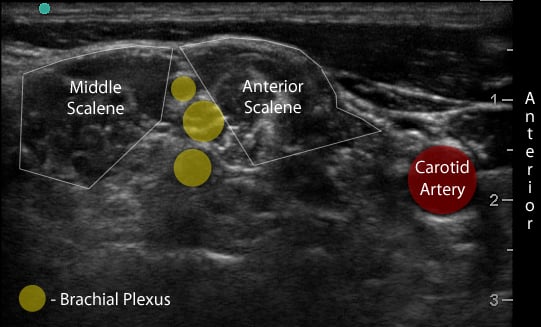

Figure 2a. Transverse view through the interscalene space

Figure 2b. With labels

- Move the probe inferiorly to identify the anterior scalene muscle deep to the lateral border of the SCM. (Figure 2)

- Identify the middle scalene muscle posterior to the anterior scalene muscle.

- The interscalene space is between these 2 scalene muscles and contains the brachial plexus

- Visualize the brachial plexus here as a stack of circles with hypoechoic centers